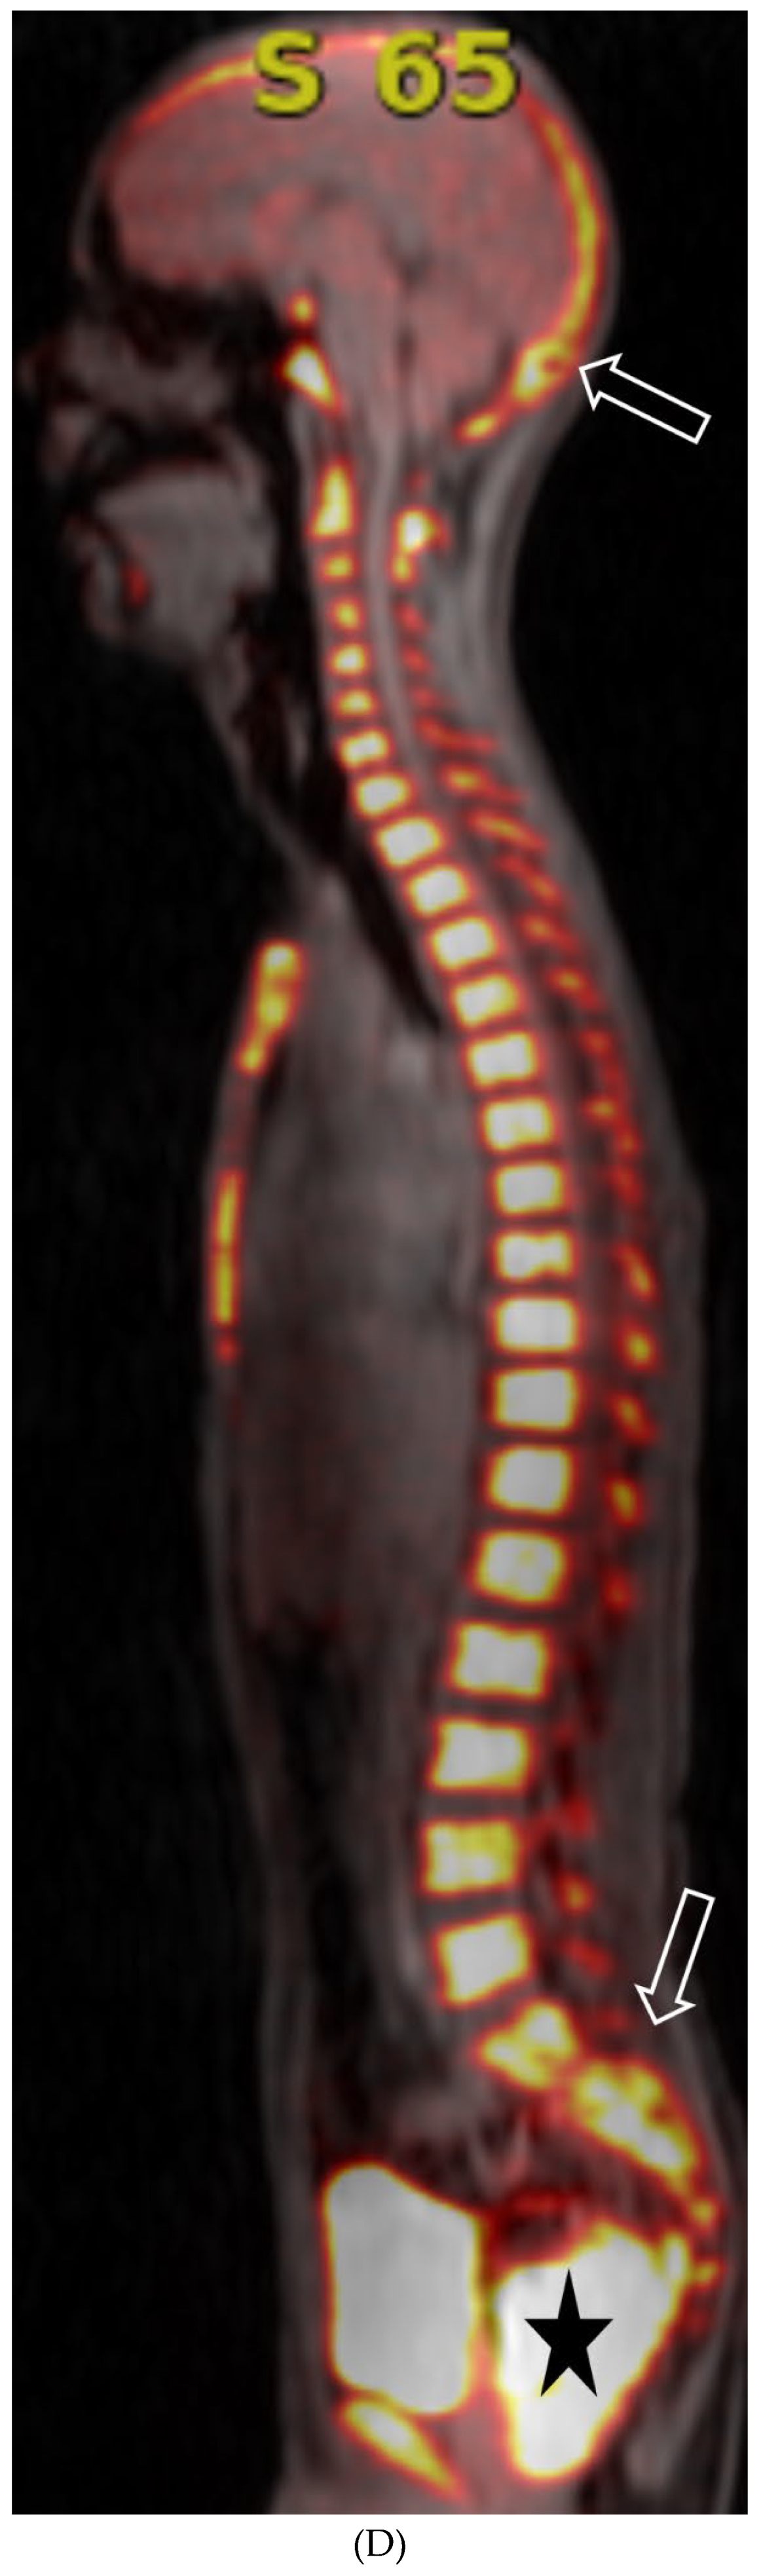

MOYA MOYA